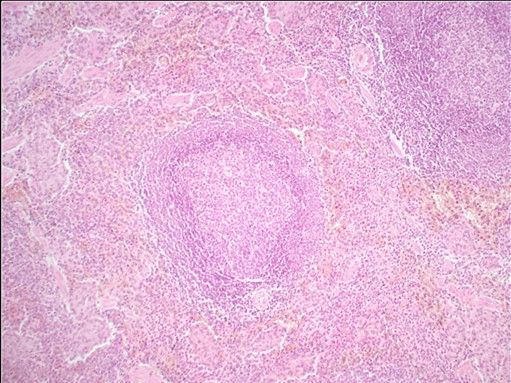

Question 8

Question

Label this image

Image:

88ba1779-3d70-4e37-86b3-21b2ff592954 (image/jpeg)

Answer

Spleen